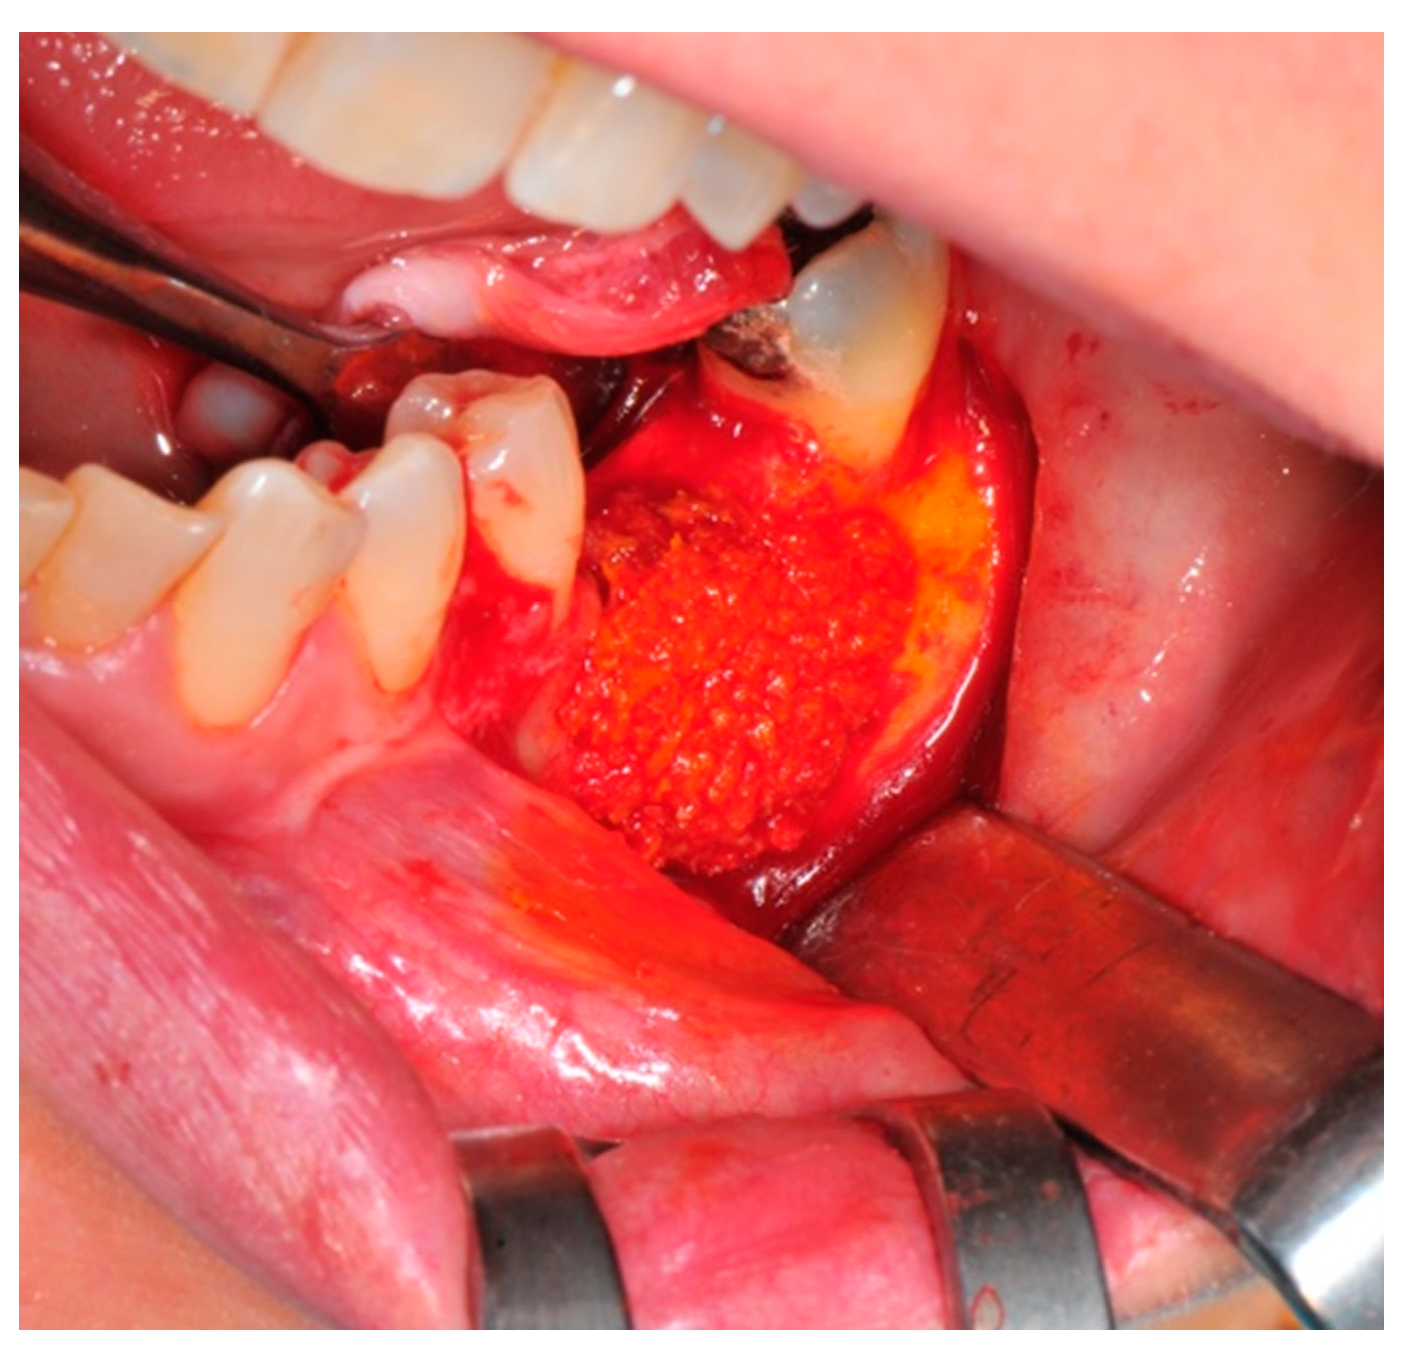

- Preparation of the receiving site: The exposed bone is cleaned from all of the remaining soft tissue and it is then prepared with multiple perforations using a small ball bur; this procedure is known as “bone refreshing” and it is performed to expose the cancellous portion of the residual bone, which shows a great osteo-genetic potential (Figure 6).